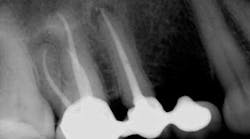

Some periapical radiolucencies (PARLs) (figure 4) may last up to five years after root canal treatment. One factor that contributes to the prolonged presence of PARLs is size of the initial lesion, such that larger lesions tend to last longer and heal at a slower rate. Location of the lesion is another factor that may contribute to this prolonged healing. Lesions in denser bone, such as the anterior mandible, tend to heal slower than lesions in less cortical bone, such as the posterior maxilla. The patient’s medical history is another factor that should be taken under consideration in such cases. Studies show that patients with diabetes, due to their lower immune system function, may require more time to heal. Some of the PAPs that tend to last can also be scar tissue in the bone.